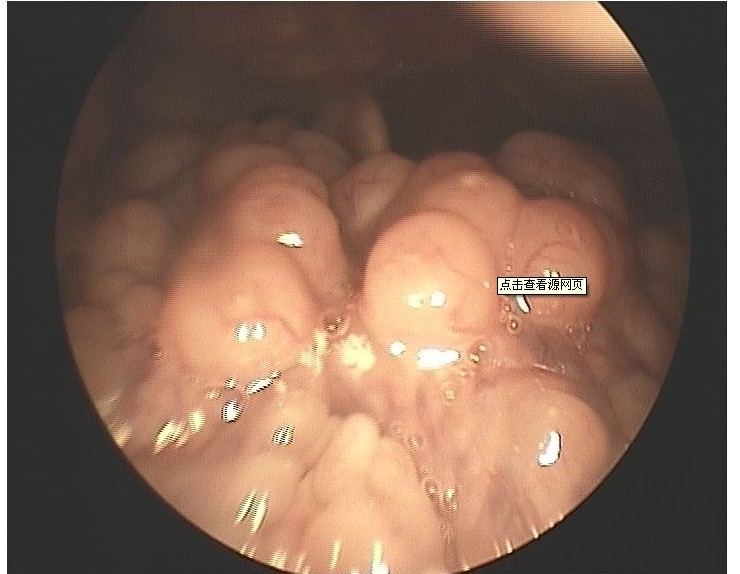

舌根淋巴滤泡增生

舌根部淋巴滤泡增生

慢性咽炎的舌根淋巴滤泡增生治的好吗鼻咽部咽隐窝正常,舌根部淋巴

【图】舌根淋巴滤泡增生的临床表现有哪些 4大症状引起病发